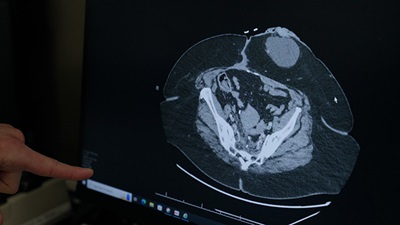

• Transanal total mesorectal excision (TaTME): We remove part or all of your rectum, along with the fatty tissue and lymph nodes around it, through your anus. We attach your colon to the remaining part of your rectum. TaTME is for select patients with hard-to-reach tumors in the mid to lower rectum.